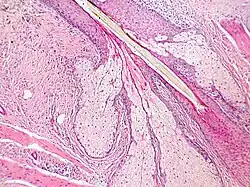

Les glandes sébacées ont une architecture acinaire (en forme de grappe de raisin) et n'ont pas de lumière propre. Elles sont composées de sébocytes matures, dont la sécrétion est le résultat de leur mort par apoptose[pas clair], ce qui revient à une sécrétion holocrine. Le remplacement des cellules est assuré par les cellules de la matrice reposant sur la membrane basale[5].L'annexe pilo-sébacée constituée du follicule pileux, des glandes sébacées et des muscles arrecteurs du poil résulte d'une invagination épithéliale[4].

Annexe pilosébacée avec glandes sébacées s'abouchant à un follicule pileux.